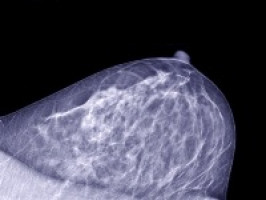

Patients with “triple negative” breast cancer (tumour cells that are hormone receptor negative and express normal levels of the HER2 oncogene) are known to be at high risk for metastatic progression.

To determine the effects of LPA1 inhibition on metastatic dormancy, Jean-Claude A. Marshall, MSc., Ph.D. of the Women’s Cancers Section, Laboratory of Molecular Pharmacology, Center for Cancer Research, NCI, and colleagues analyzed primary tumour size, distant metastases and their molecular characteristics in two model systems of aggressive “triple negative” breast cancer metastasis, the murine 4T1 mammary carcinoma model and human MDA-MB-231 human breast carcinoma model. Debio-0719 or shRNA knockdown of LPA1 significantly inhibited metastasis formation without affecting primary tumour size.